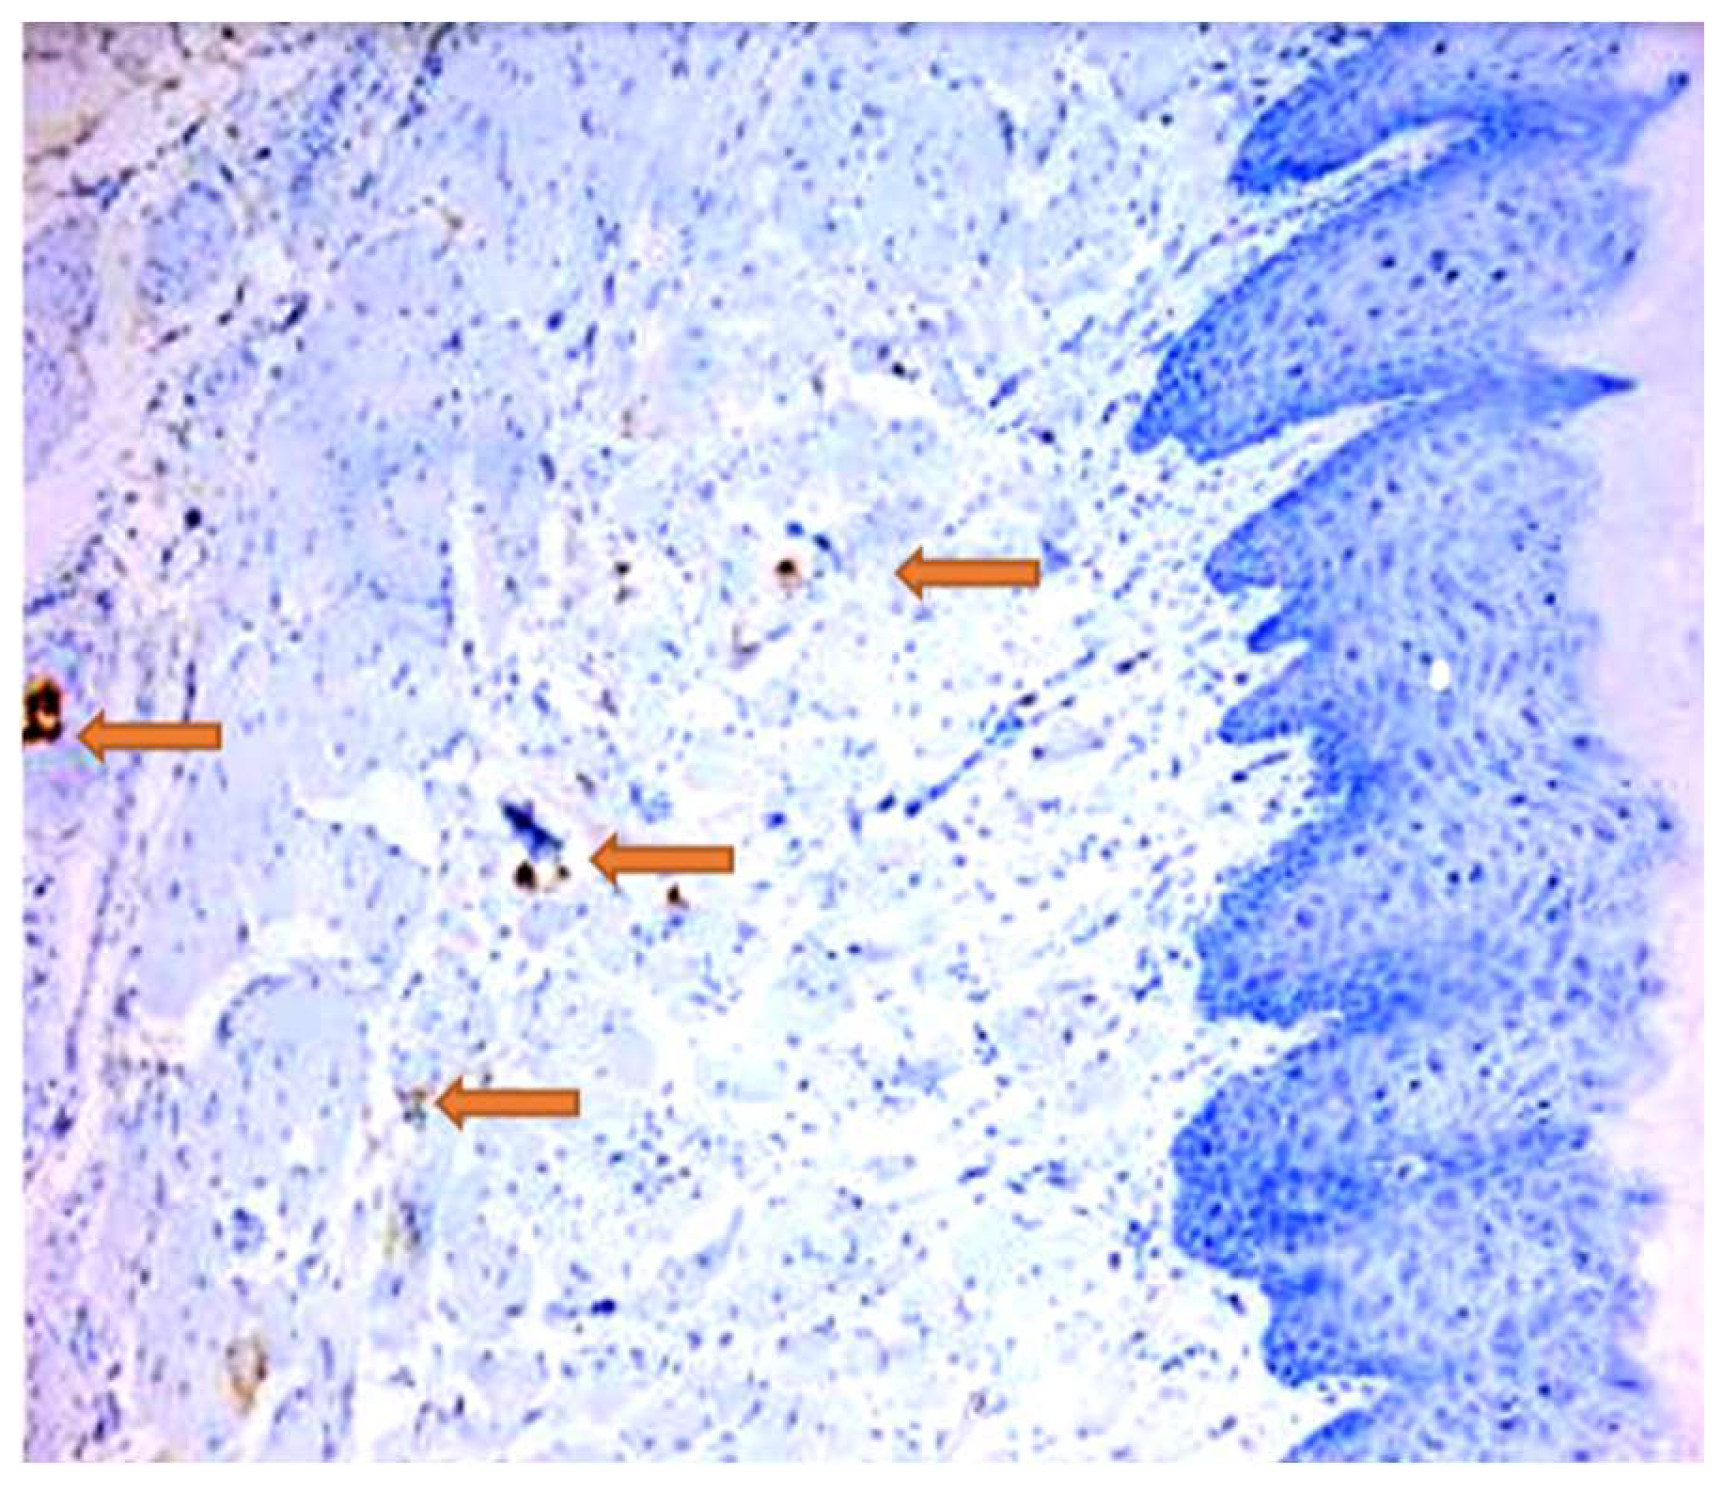

- Roi, C.; Gaje, P.N.; Ceaușu, R.A.; Roi, A.; Rusu, L.C.; Boia, E.R.; Boia, S.; Luca, R.E.; Riviș, M. Heterogeneity of Blood Vessels and Assessment of Microvessel Density-MVD in Gingivitis. J. Clin. Med. 2022, 11, 2758. [Google Scholar] [CrossRef]

| Antibody | Epitop/Marker | Manufacturer | Antigenic Unmasking | Dilution |

|---|---|---|---|---|

| CD3 | T lymphocytes | DAKO | Citrate buffer pH = 6 | 1:100 |

| CD20 | B lymphocytes | DAKO | Citrate buffer pH = 6 | 1:50 |

| CD34 | Endothelial cells | DAKO | Citrate buffer pH = 6 | 1:50 |

| Group | T CD3+ Cells | B CD20+ Cells | Total CD34+ Cells | Mature CD34+ Cells | Imature CD34+ Cells |

|---|---|---|---|---|---|

| Control | 3 | 2.5 | 17.5 | 7 | 10.5 |

| DP | 55.5 | 6 | 13.5 | 4 | 9.5 |

| DPCu | 41 | 3.5 | 25 | 4.5 | 20.5 |

| DPR | 15 | 6.5 | 7 | 2.5 | 4.5 |

| DPCuR | 2 | 0.5 | 8 | 3 | 5 |